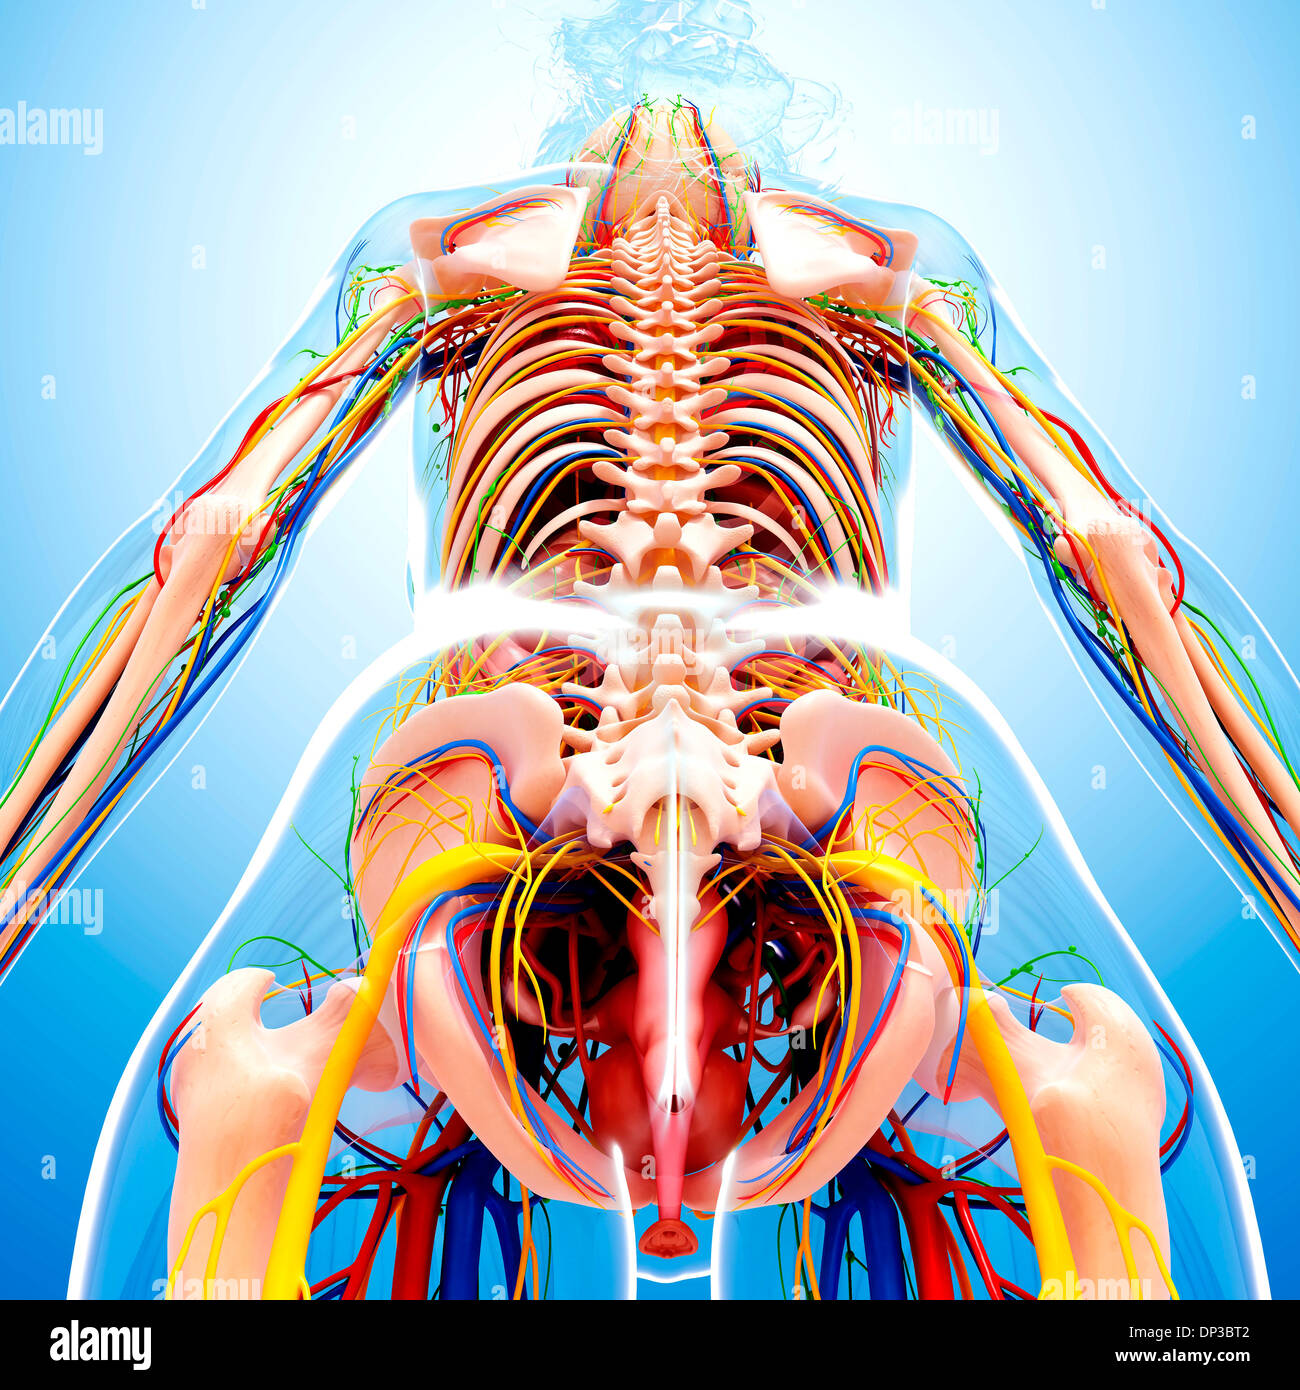

female anatomy art Complete female anatomy 3d model

fineartamerica.comFemale Anatomy, Artwork Stock Photo - Alamy

fineartamerica.comFemale Anatomy, Artwork Stock Photo - Alamy

fineartamerica.comFemale Anatomy, Artwork Stock Photo - Alamy

fineartamerica.comFemale Anatomy, Artwork Stock Photo - Alamy

www.alamy.comFemale Anatomy, Artwork Stock Photo - Alamy

www.alamy.comFemale Anatomy, Artwork Stock Photo - Alamy

bocadowasubo.github.ioFemale Anatomy, Artwork Stock Photo - Alamy

bocadowasubo.github.ioFemale Anatomy, Artwork Stock Photo - Alamy

fineartamerica.comFemale Anatomy, Artwork Stock Photo - Alamy

fineartamerica.comFemale Anatomy, Artwork Stock Photo - Alamy

www.etsy.comFemale Anatomy, Artwork Stock Photo - Alamy

www.etsy.comFemale Anatomy, Artwork Stock Photo - Alamy

www.alamy.comFemale Anatomy, Artwork Stock Photo - Alamy

www.alamy.comFemale Anatomy, Artwork Stock Photo - Alamy

www.alamy.comFemale Anatomy, Artwork Stock Photo - Alamy

www.alamy.comFemale Anatomy, Artwork Stock Photo - Alamy

fineartamerica.comFemale Anatomy, Artwork Stock Photo - Alamy

fineartamerica.comFemale Anatomy, Artwork Stock Photo - Alamy

Female Anatomy, Artwork Stock Photo - Alamy

www.alamy.comFemale Anatomy, Artwork Stock Photo - Alamy

www.alamy.comFemale Anatomy, Artwork Stock Photo - Alamy

www.etsy.comFemale Anatomy, Artwork Stock Photo - Alamy

www.etsy.comFemale Anatomy, Artwork Stock Photo - Alamy

www.alamy.comFemale Anatomy, Artwork Stock Photo - Alamy

www.alamy.comFemale Anatomy, Artwork Stock Photo - Alamy

www.alamy.comFemale Anatomy, Artwork Stock Photo - Alamy

www.alamy.comFemale Anatomy, Artwork Stock Photo - Alamy

Female Anatomy, Artwork Stock Photo - Alamy

www.alamy.com3d Rendered Illustration Of The Female Anatomy Stock Photo - Alamy

www.alamy.com3d Rendered Illustration Of The Female Anatomy Stock Photo - Alamy

fineartamerica.com3d Rendered Illustration Of The Female Anatomy Stock Photo - Alamy

fineartamerica.com3d Rendered Illustration Of The Female Anatomy Stock Photo - Alamy

pixels.comFemale Anatomy, Artwork Stock Photo - Alamy

pixels.comFemale Anatomy, Artwork Stock Photo - Alamy